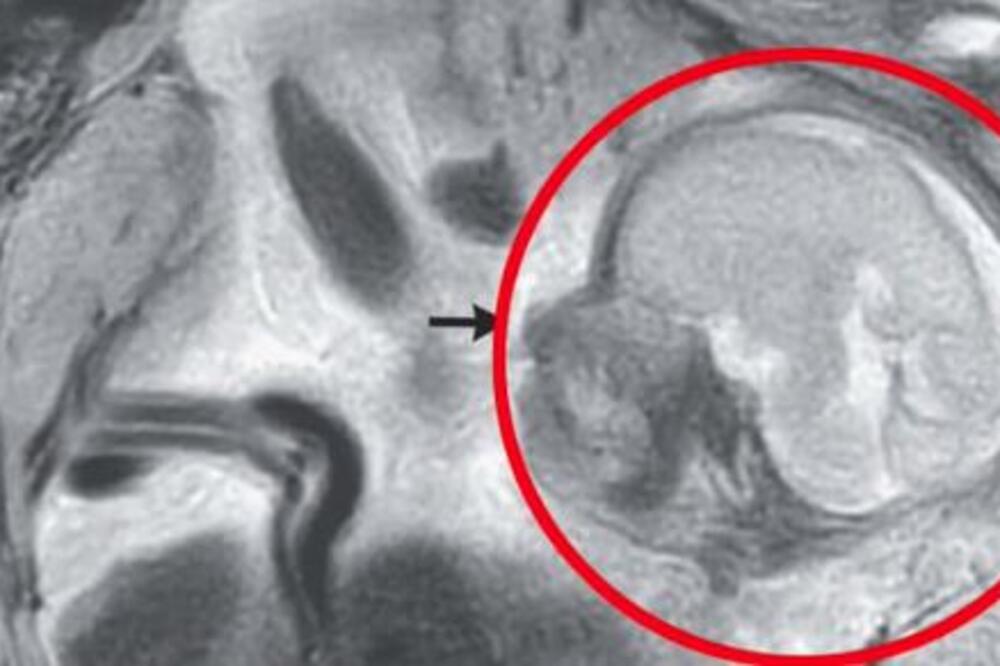

Naime, utvrđeno je da u trbušnoj duplju, tačnije prostoru između želuca i creva, postoji pravilno formiran fetus.

Reč je o retkom obliku vanmaterične trudnoće, dok je placenta bila pričvršćena za vrh karlice, prenosi Daily Mail.